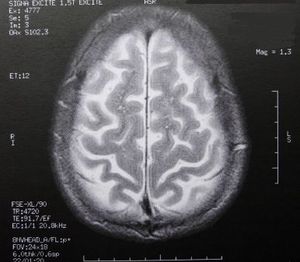

Hirn durchleuchtet: Informationen nicht sicher (Foto: pixelio.de, Dieter Schütz)